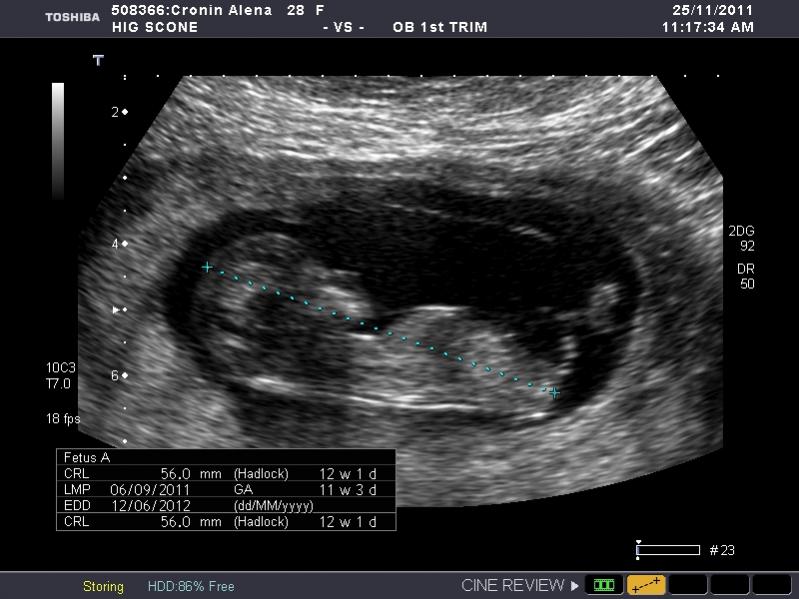

I have heaps of photos and I don't know what I am looking at so if the photo I post isn't showing anything let me know and I will try another. I am nervous as anything because I so so want a girl, but of course would still be happy with a boy. The ultrasound tech wouldn't guess.

So what is your guess.